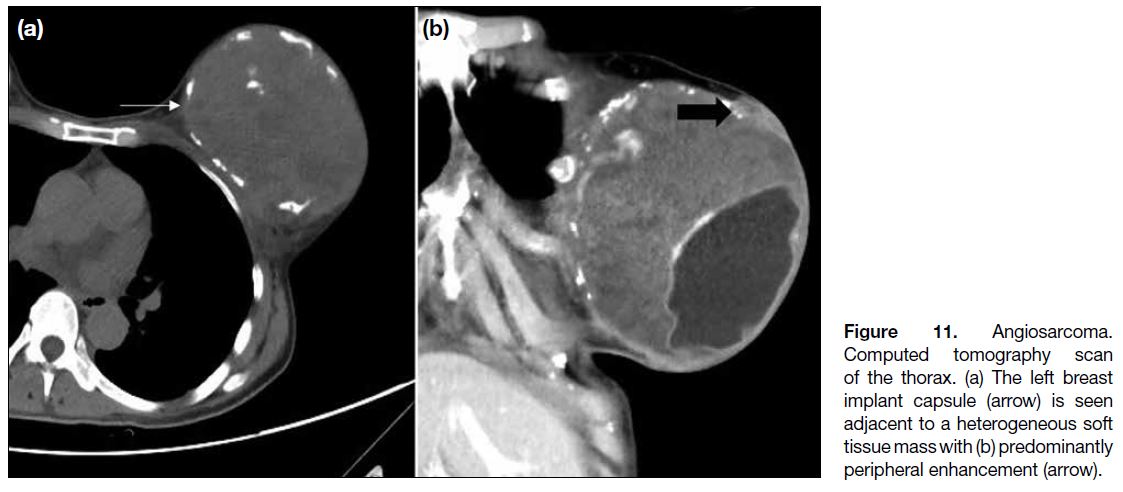

In our case, similar to other breast tumours, angiosarcomas

may enhance after contrast administration on computed

tomography scan (Figure 11).

Figure 11. Angiosarcoma.

Computed tomography scan of

the thorax. (a) The left breast implant

capsule (arrow) is seen

adjacent to a heterogeneous soft

tissue mass with (b) predominantly

peripheral enhancement (arrow).